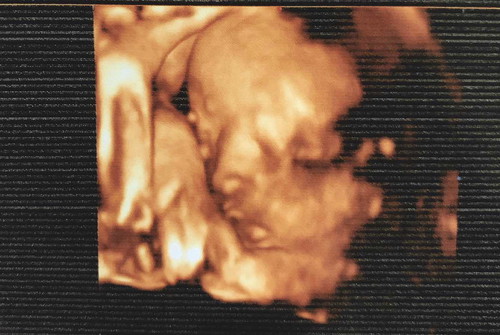

สวัสดีค่ะ พอดีท้องแรกค่ะ อยากสอบถามแม่ๆที่คลอดธรรมชาติว่า บรรยากาศระหว่างการคลอดเป็นยังไงบ้างคะ ความกลัว ความเจ็บปวด เป็นอย่างไรกันบ้างคะ จะครบกำหนดคลอด 19/6/63 นี้ ตื่นเต้นมากๆค่ะ ??